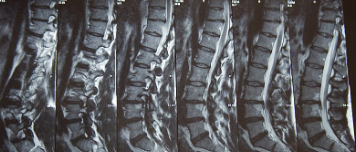

허리디스크를 올바르게 진단할려면 엑스레이로는 힘들며, MRI를 통해 검사해야 올바르게 볼 수 있습니다.

MRI가 몸에 좋지 않지만 허리 통증으로 엑스레이만 진행 할 경우 오진이 많아 계속적인 고통이 계속 된다면 허리디스크를 의심하고 MRI 검사를 한번 받아보시길 권유드립니다.